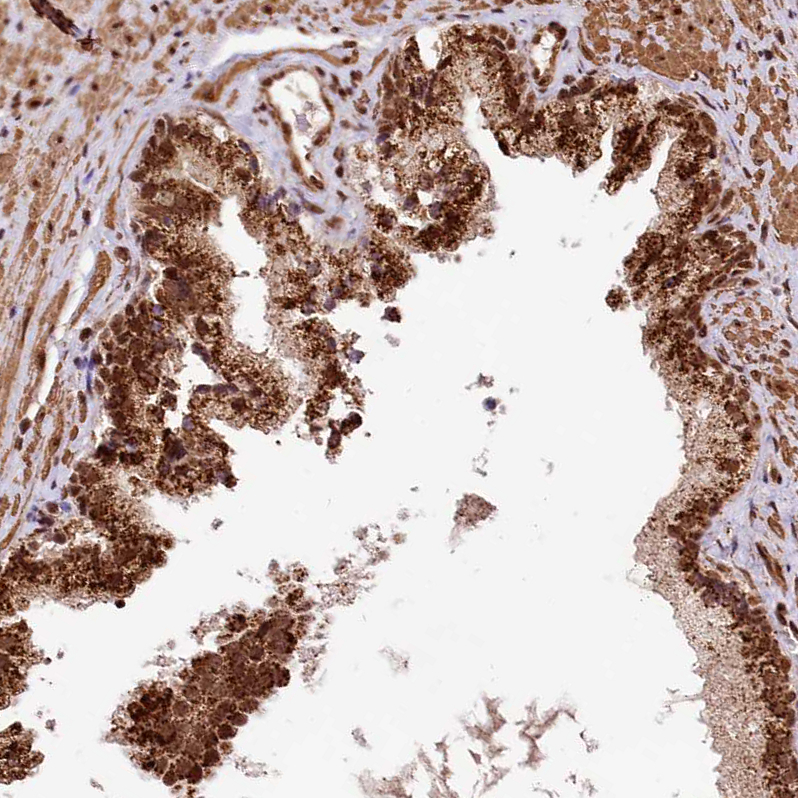

Immunohistochemical staining of human Testis shows strong nuclear positivity in cells in seminiferous ducts and Leydig cells.